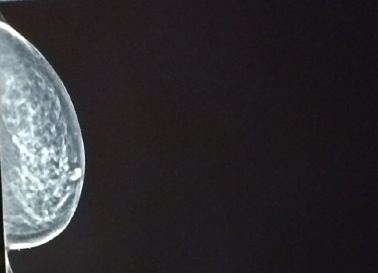

今天被医生招呼来做mammogram,看着奶子被机器压来压去的左照又照怪不舒服。医生身上带了一个自行车胸针,我想问问这是什么运动的标记,由于病人身份所以我审慎的不敢乱搭讪。在被挤压的过程中,我琢磨出一点道理,他们的就是要压出哪里有噪点。就算怀着再不懂的心,扭头使劲回望,噪点连我自己都看懂了。

之后我又被叫去做B超, 光这两种检查我就被跌跌撞撞折腾好几个来回. 有图为证。

我忍不住开口问了为什么照这么多次,心想既来之就要整明白不是。你看天下的事情往往都是一厢情愿。我一追问结果就出来了,据说右边,左边都发现肿瘤 , 他们的结果让我连给自己留余地的地方都没有了。当然还有一种可能,右边是恶性,左边是良性,被专家们折腾成这么样,我也不敢轻易放狠话了,任他们折腾我保留了心理那一分从容。